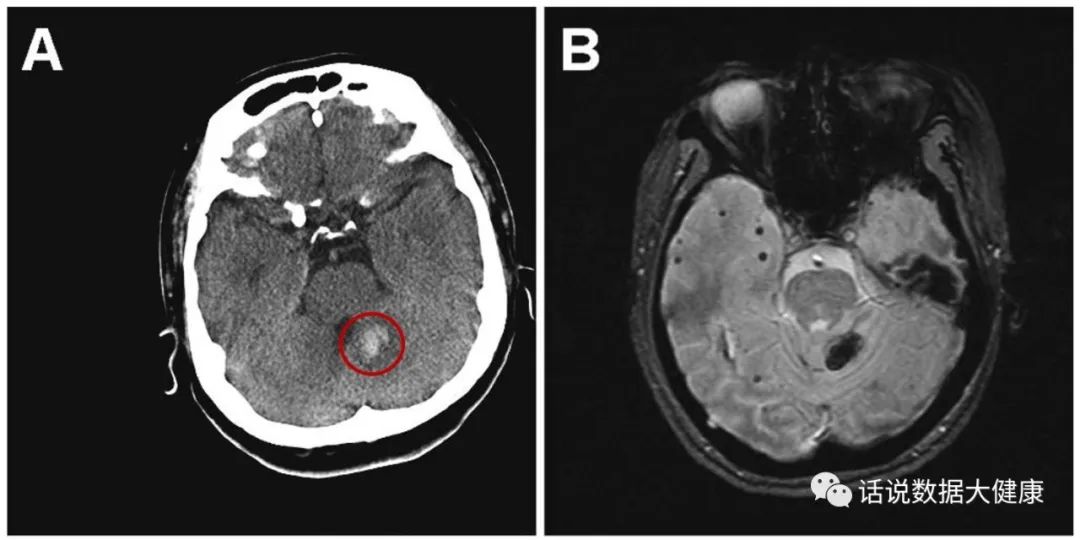

服用纳豆安全吗?目前美国食品和药物管理局认为服用纳豆(纳豆激酶)产品并不是普遍安全的。加拿大卫生部认定纳豆激酶有增加出血的潜在风险。某女性,52岁,患有高血压,1年前查体时发现有腔隙性脑梗塞,每天服用降压药和100mg阿司匹林,听闻纳豆保健品中宣传内容后,1周前开始 服用纳豆激酶400mg/天预防脑卒中 ,出现了眩晕和站立不稳,经检查出现急性小脑出血和多发散在出血灶。